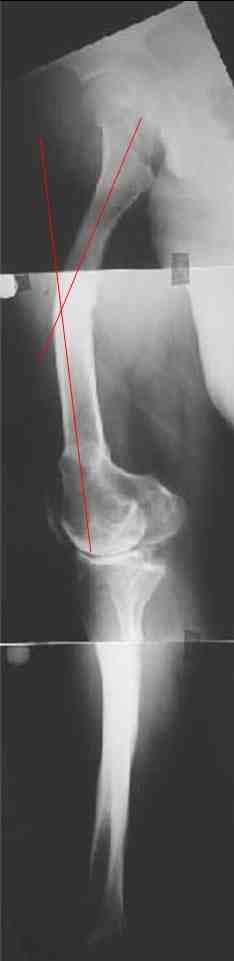

В данном случае перед эндопротезированием мы бы корригировали оси бедренной и большеберцовой костей (см. вложение). Дистальный эпидиафизарный угол бедра будет корригирован при эндопротезировании. Тип остеотомии и коррекции деформации (клиновидная резекция - одномоментная коррекция; формироване треугольных или трапециевидных регенератов во времени) - исходя из

относительной длины конечности.